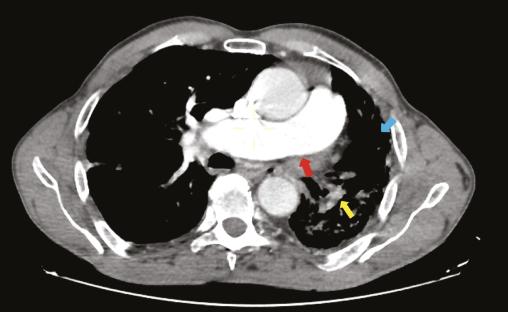

Un homme âgé de 66 ans, sans antécédents particuliers, est admis aux urgences pour la prise en charge d’un traumatisme thoracique minime. Une radiographie thoracique montre une asymétrie de taille des deux champs pulmonaires avec une déviation médiastinale vers la gauche (fig. 1). Un angioscanner thoracique montre une agénésie de l’artère pulmonaire gauche, une hypoplasie du poumon homolatéral et des lacérations vasculaires systémiques d’origine bronchique vascularisant le poumon gauche (fig. 2).

Le diagnostic repose classiquement sur l’angiographie, mais l’angioscanner reste l’examen de référence  : il montre l’absence de structure vasculaire sur le trajet de l’artère pulmonaire, avec une paroi lisse et régulière entre l’artère pulmonaire primitive et l’artère pulmonaire droite ou gauche résiduelle, et permet également d’objectiver une éventuelle hypoplasie associée.5